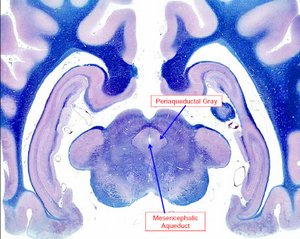

El mesencéfalo o encéfalo medio se originan el nervio oculomotor (III) y troclear (IV), y contiene el acueducto mesencefálico por el que circula el LCR.

La materia gris periacueductal juega una importante función en la modulación del dolor.

detalle histológico de un corte axial del mesencéfalo